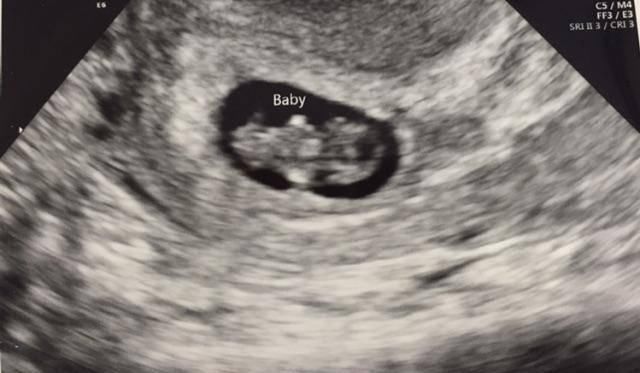

B超检查

第一次产检做B超是最重要的,这项检查可以看到胎儿的发育情况,孕妈妈可以选择阴超也可以选择腹部B超。

本次检查主要看孕囊、胎心和胎芽。

1、孕囊

孕囊是原始的胎盘组织,是怀孕最初的形态。如果孕囊在宫内,就能确定是宫内孕,属于正常怀孕。孕囊的尺寸一般在1.33厘米-1.66厘米,有椭圆形的也有圆形的。